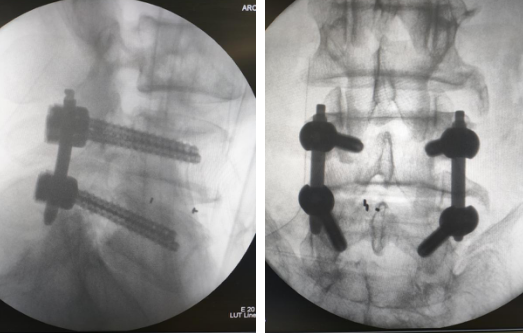

详细的术前准备后,尚军主任张冶副主任医师团队为老人进行了“腰椎后路减压+内固定+融合术”,术中,手术医生利用C型臂对患者进行三维影像扫描,图像被同步传输至手术机器人系统;进行L4/5椎弓根定位并在皮肤表面标记;在机器人的精确定位下置入导针,行L4/5椎管扩大减压处理,切除L4下关节突,L5上关节突,切除部分黄韧带,显微镜下摘除L4/5髓核,处理L4/5椎间盘及终板,在机器人辅助下,精准安装椎弓根钉,椎体后方植骨。手术切口仅3厘米,基本不造成患者肌肉软组织损伤,手术时间也大幅缩短。术后老人的腰痛和左腿的痛麻消除,在脊柱病区康复,很快能下地行走。